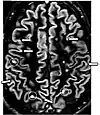

| Diffusion weighted (DWI) | Conventional | DWI | Measure of Brownian motion of water molecules.[74] | High signal within minutes of cerebral infarction (pictured).[75] | ![]() |